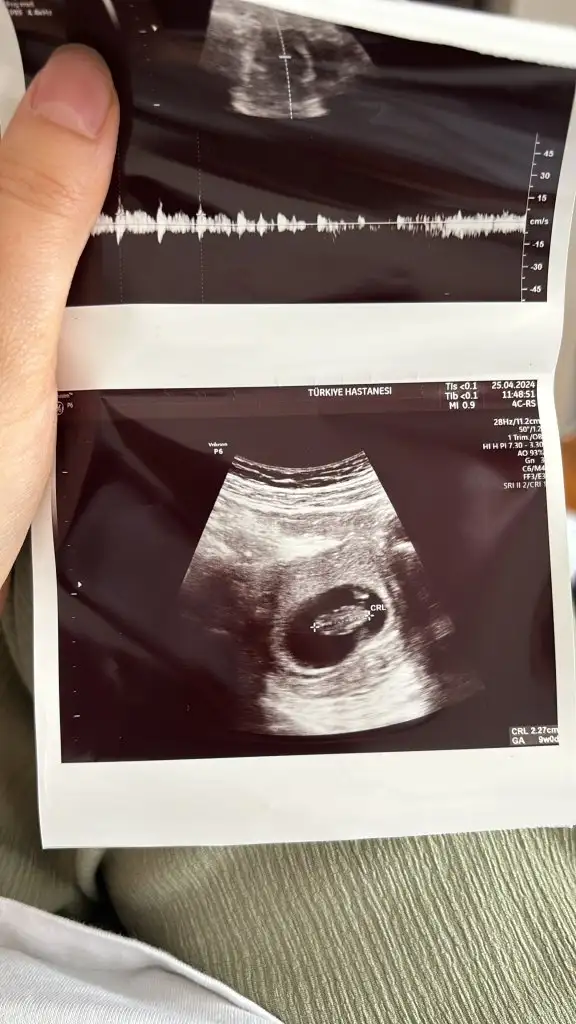

Benimkine de bakar mısınız? 10+2 Selisay

Eklentiler

• IMG_20240422_124357.webp

8,3 KB · Görüntüleme: 94